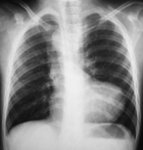

1. A 37-year-old man, with no known medical illness, came for a routine medical check-up. His chest radiograph is presented to you. Identify the incorrect statement with respect to the X-ray shown below.

1. The structure marked as number 2 is right ventricular border

2. The structure marked as 1 is the trachea

3. The structure marked as 3 is the left ventricular border

4. The structure marked as 4 is the aortic arch